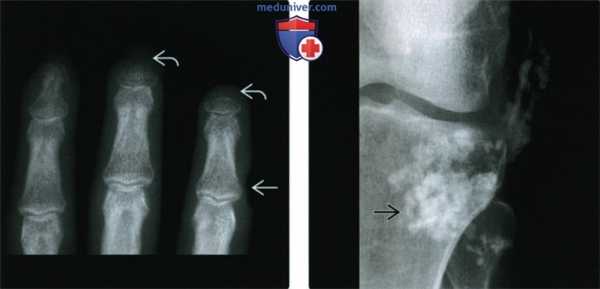

• Акроостеолиз (40-80%):

о Резорбция ногтевых бугристостей, истончение, со временем развивается резорбция всей дистальной фаланги

(Слева) Рентгенография в ЗП проекции: определяется изъязвление мягких тканей и конусообразное сужение мягких тканей пальцев в сочетании с акроостеолизом. Мягкие ткани также сужаются конусообразно. Такая тяжеля степень акроостеолиза может развиваться на средней или поздней стадиях ПСС.

(Справа) Рентгенография в ПЗ проекции: у пациента с ПСС определяется почти листовидный кальциноз мягких тканей, что может наблюдаться при дерматомиозите. Такая картина неспецифична.

(Слева) Рентгенография в ЗП проекции: в области пальцев определяется ранняя стадия акроостеолиза с сопутствующим конусообразным сужением мягких тканей, а также шаровидные кальцификаты В в мягких тканях. Хотя оба этих признака могут наблюдаться при ГПТ, признаки поднадкостничной резорбции отсутствуют, что делает наиболее вероятным диагноз ПСС.

(Справа) Рентгенография в косой проекции при ПСС в поздней стадии: определяется акроостеолиз и шаровидные кальцификаты мягких тканей. Имеется контрактура 2-4 пальцев. Такое сочетание признаков может наблюдаться при ожоговой травме, но диагностирован ПСС. (Слева) Рентгенография в ЗП проекции: классическая картина прогрессирующего системного склероза, или склеродермии в поздней стадии. Наблюдается выраженный кальциноз мягких тканей как в подкожно-жировой клетчатке, так и в околосуставной области. Обратите внимание на акроостеолиз, наиболее выраженный в третьем пальце. Имеются эрозии ДМФС-часто встречающийся признак ПСС в поздней стадии.